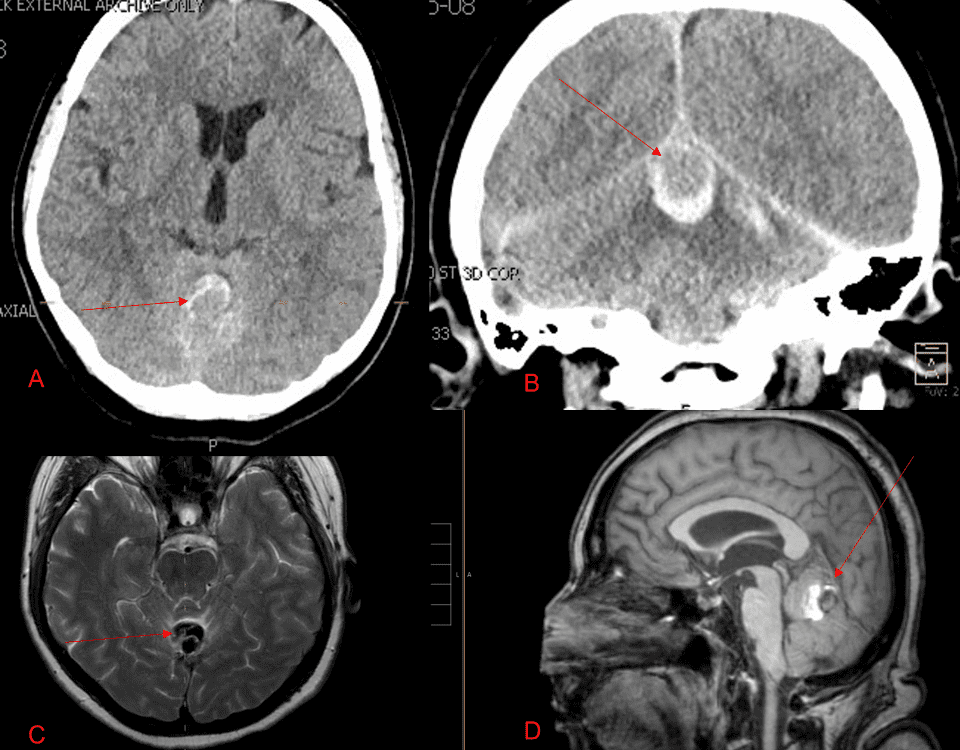

A 55-year-old woman presented with acute onset of severe headache, and possible witnessed seizure. Imaging confirmed intraventricular hemorrhage primarily focused within the fourth ventricle with diffuse […]

Case Presentation: A woman in her 80s developed mild dizziness and headache following incidental trauma working in her garage one day. She presented several weeks later […]

This is a 49-year-old otherwise healthy female who presented with bifrontal and retro-orbital headaches, behavioral changes, and forgetfulness. Symptoms have been progressively worsening over the past […]